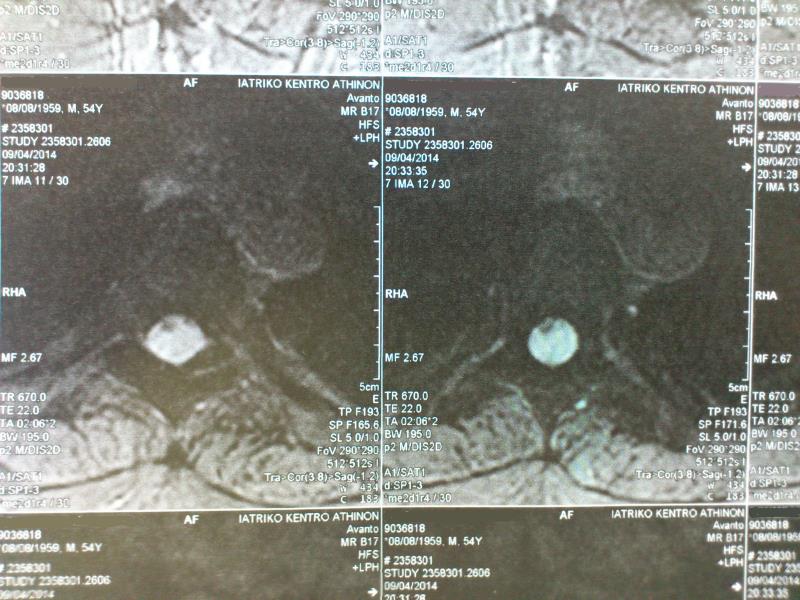

Ασθενής άνδρας 54 ετών με ιστορικό μυϊκής αδυναμίας και αισθήματος αιμωδιών κάτω άκρων από 4ετίας με προοδευτική επιδείνωση και εμφάνιση επιπροσθέτως διαταραχών σφιγκτήρων  παραπέμφθηκε στην κλινική μας μετά από τη διενέργεια MRI ΘΜΣΣ που ανέδειξε εικόνα πρόσθιας κήλης νωτιαίου μυελού στο επίπεδο Θ5-Θ6. Ο ασθενής υποβλήθηκε σε οπίσθια προσπέλαση. Μετά από διατομή αμφοτερόπλευρα των οδοντωτών συνδέσμων και της ραχιαίας αριστερής Θ5 ρίζας αναγνωρίσθηκε πρόσθια κήλη του νωτιαίου μυελού μέσα από έλλειμμα οπισθίου πέταλου διπλής (duplicate ) κοιλιακής (ventral) σκληράς μήνιγγας.Με μικροχειρουργική τεχνική επιτεύχθηκε διεύρυνση του ελλείμματος με αφαίρεση του οπισθίου πετάλου πέριξ αυτού και τελική ανάταξη του νωτιαίου μυελού.Ο ασθενής είχε ομαλή μετεγχειρητική πορεία και εξήλθε παρουσιάζοντας βελτίωση της μυϊκής ισχύς των κάτω άκρων. Η μετεγχειρητική μαγνητική τομογραφία ανέδειξε  ανάταξη του νωτιαίου μυελού με σήμα μυελοπάθειας στο επίπεδο της κήλης. Η χειρουργική αντιμετώπιση ασθενών με ιδιοπαθή κήλη του νωτιαίου μυελού έχει απόλυτη ένδειξη στην περίπτωση εμφάνισης μυϊκής αδυναμίας και προοδευτικής μυελοπάθειας και συνιστάται στην ανάταξη του νωτιαίου μυελού και την διεύρυνση ή αποκατάσταση του ελλείμματος της σκληράς μήνιγγος. Συνολικά οι ασθενείς τείνουν να βελτιώνονται μετά το χειρουργείο ακόμα και σε περιπτώσεις μακρόχρονου ιστορικού μυελοπάθειας.

Προεγχειρητικός απεικονιστικός έλεγχος